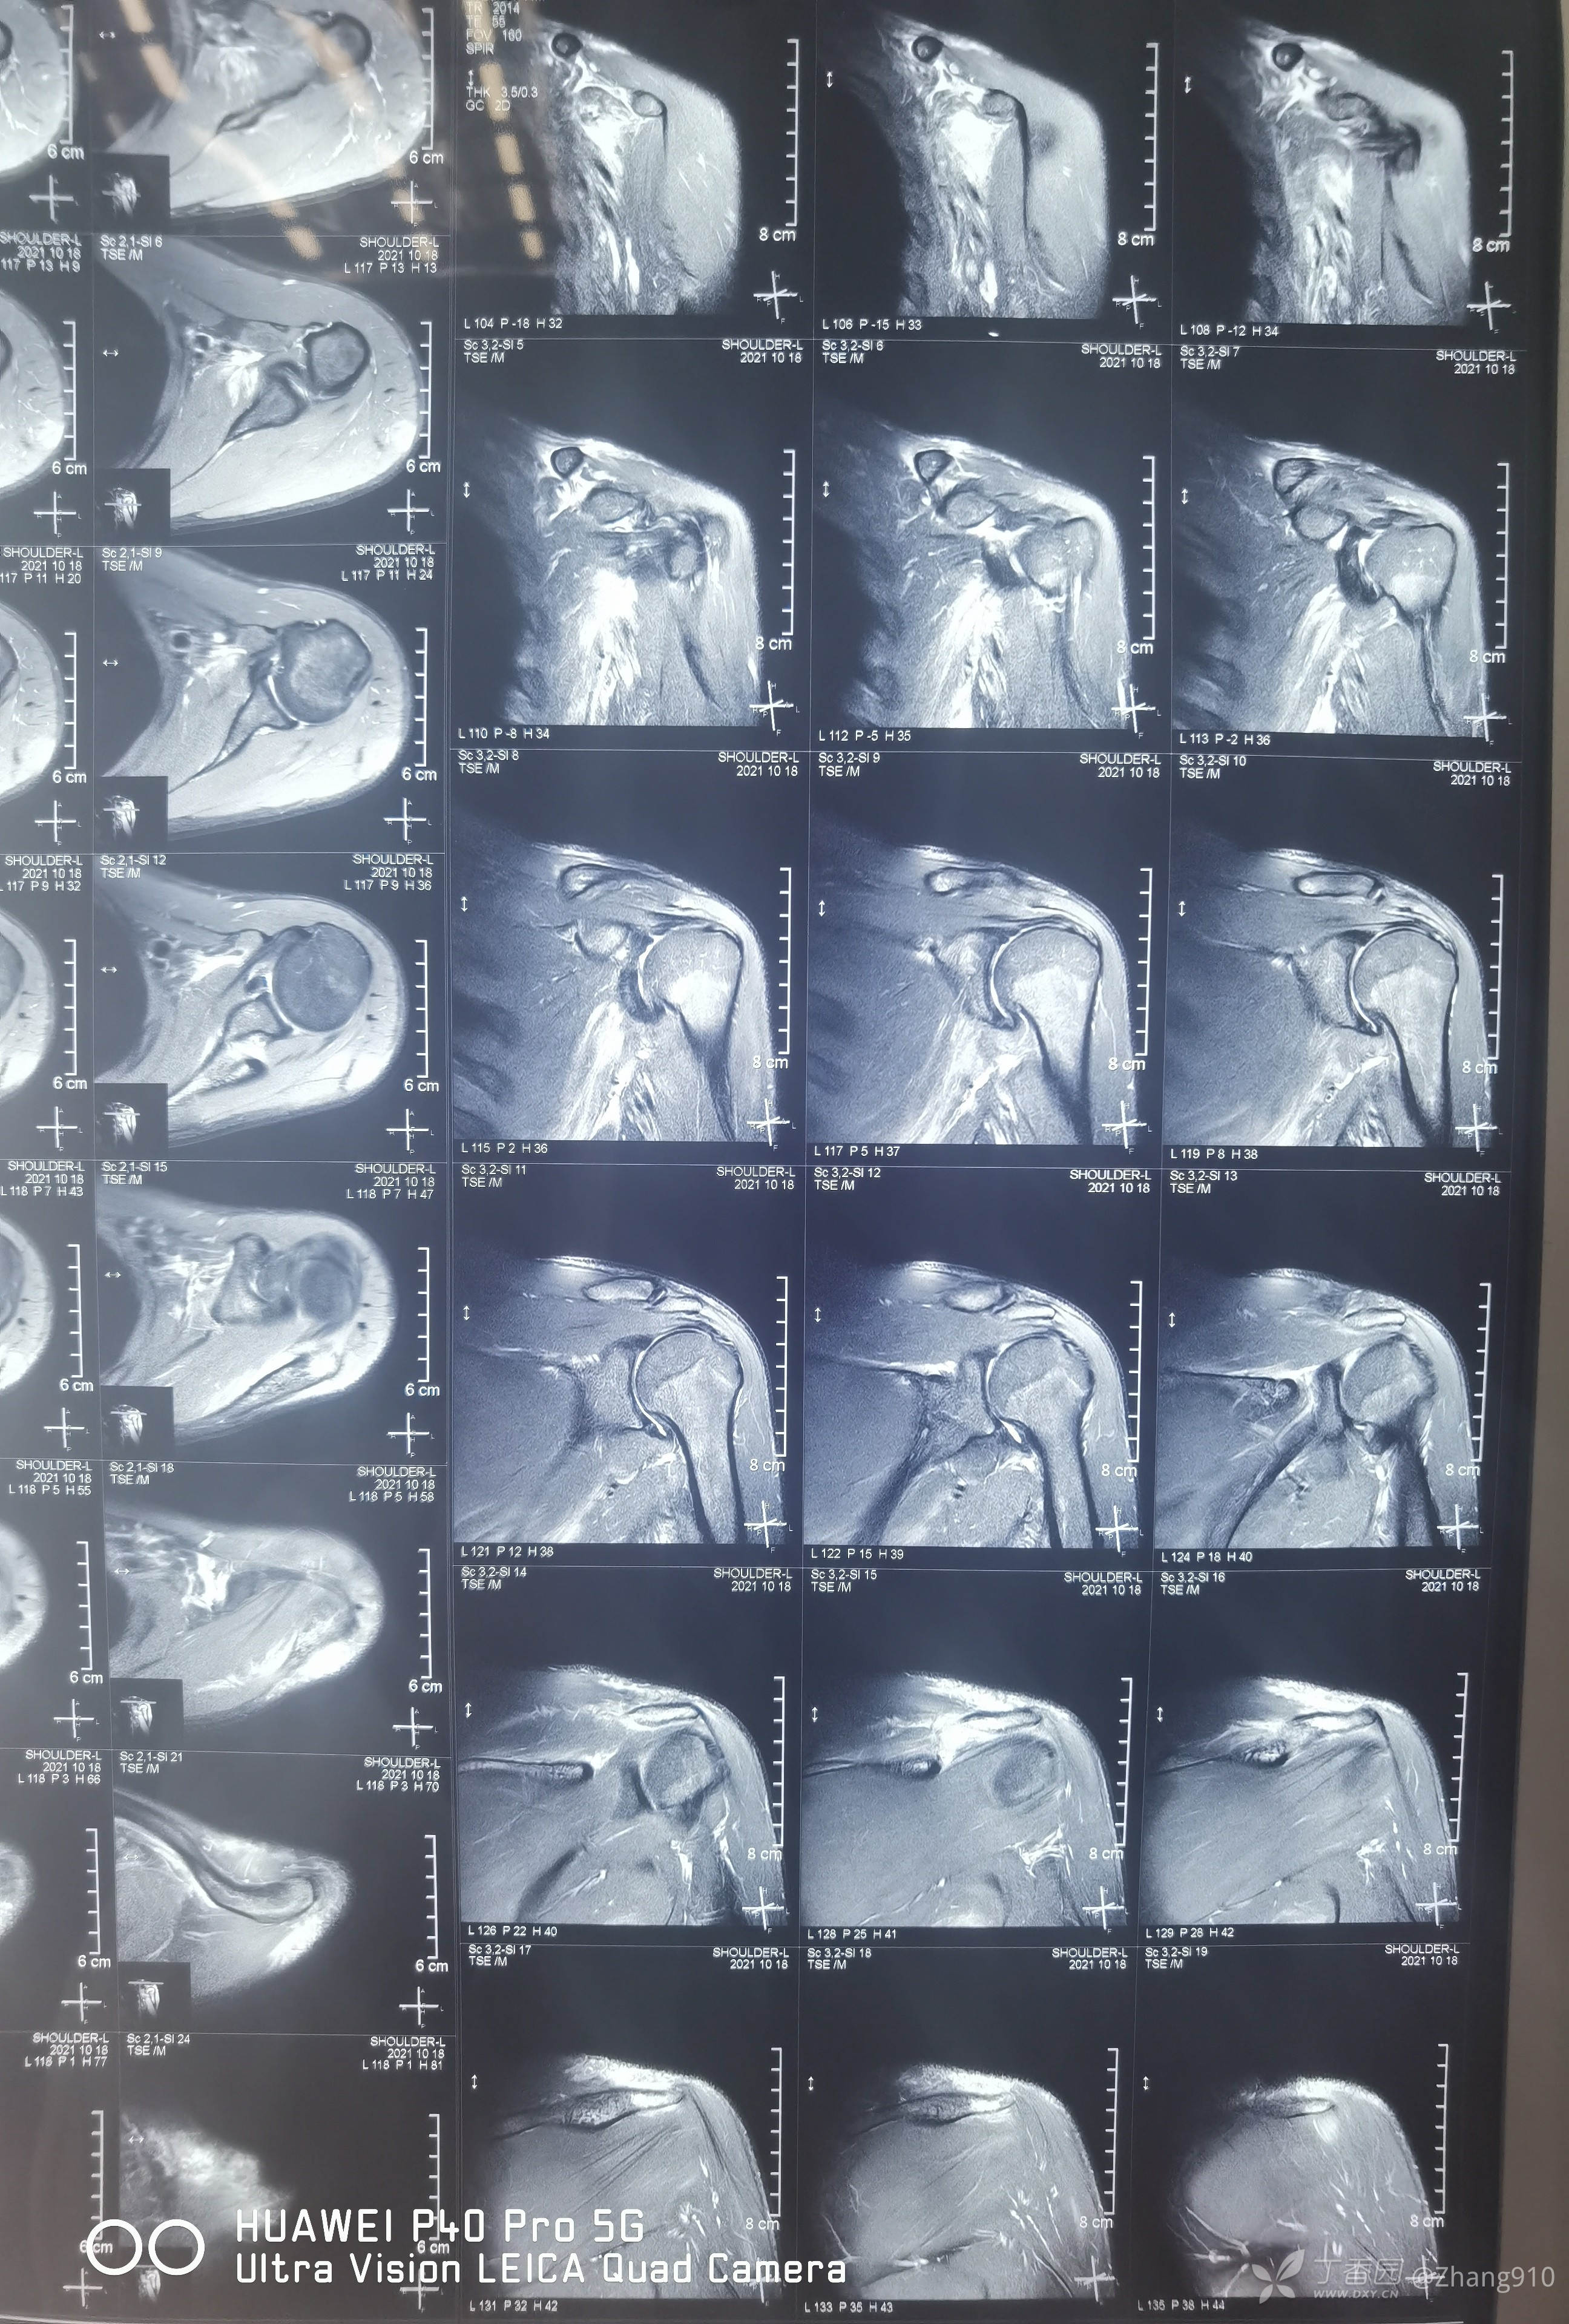

肩关节核磁共振:

核磁显示:冈上肌腱连续性可,三角肌,肩胛下肌肿胀。

目前查体,肩关节外展功能丧失,局部无压痛,核磁显示,冈上肌无断裂。肩关节没有手术指征?